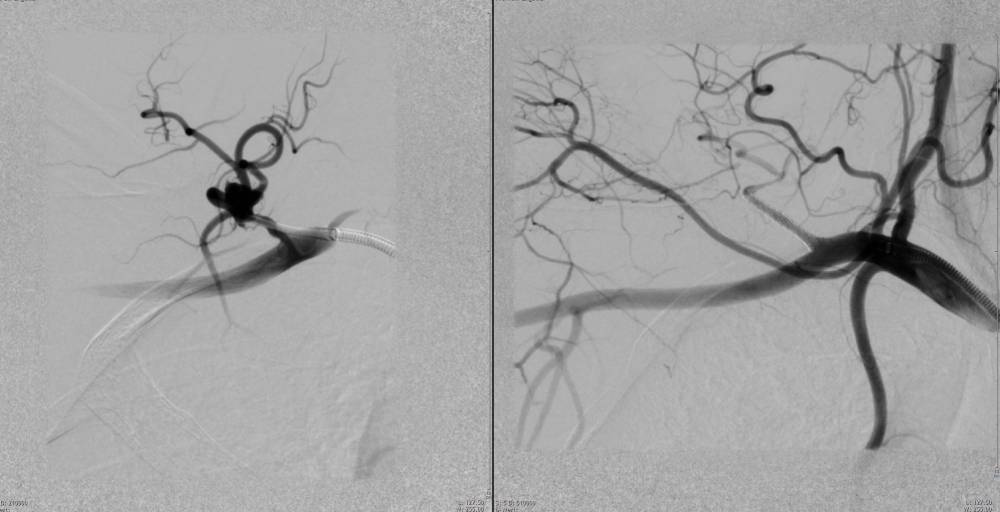

Beispiele für vaskulär-interventionelle Therapien sind endovaskuläre Prozeduren zur Gefäßreparatur (am häufigsten Aneurysmata, Defekte mit akuten Blutungen oder Verschlüssen). Hier kommen Gefäßprothesen, sogenannte Stentgrafts, oder auch Materialien zum Verschluss von Defekten, am häufigsten ebenso Gefäßprothesen, aber auch Spiralen, Klebstoffe und Partikel zum Einsatz. Dem gegenüber stehen rekanalisierende Verfahren, die zum Ziel haben, pathologisch verengte oder verschlossene Gefäße mit physiologischem Durchmesser zu rekonstruieren bzw. zu rekanalisieren. Hierbei kommen neben mechanischen Verfahren mit Ballondilatation (PTA in verschiedenen mechanischen Anwendungsarten) oder Stents oder mechanischen Spezialverfahren (Aspiration, Rotations-basierte Rekanalisation) pharmakologische Eingriffe zum Auflösen (Lyse) von verschließenden Thromben zum Einsatz oder antiproliferative Beschichtungen zur Vorbeugung einer sog. Neointimabildung zum Einsatz.

Schwarz-weiße medizinische Bildgebung, möglicherweise Angiogramm, zeigt Blutgefäße mit Kontrastmittel.

Röntgenaufnahme der Aorta mit Kontrastmittel, zeigt den Blutfluss und mögliche Anomalien.